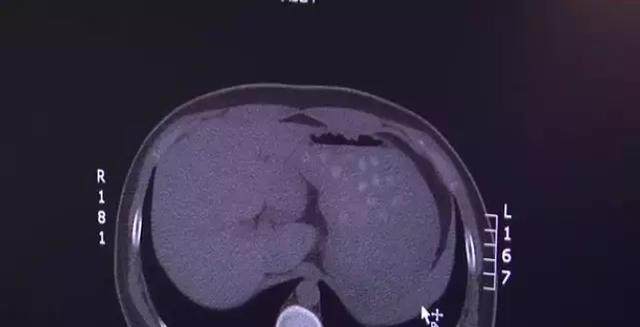

医生立即给这个男孩儿做了腹部CT检查,CT片子让医生吃了一惊,从片子上可以看到,男孩儿的胃里,竟然出现了好多圆形的小白点儿。

医师:”全是一些圆状的、不易消化的一些东西 ,大概能有三四十粒 而且胃扩张的特别大,胆囊也能明显看出增大了,所以这小孩儿我们当时就诊断为急性胆囊炎,后期追问病史,小男孩儿说当天喝了两杯珍珠奶茶,我们确定CT显示的这些圆形物体就是珍珠奶茶里的珍珠。“